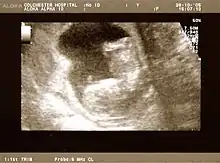

التصوير هو وسيلة أخرى هامة لمراقبة الحمل. يتم تصوير كلا من الأم والجنين عادة في الثلث الأول من الحمل. هذا ويتم اجراء ذلك للتنبؤ بالمشاكل التي مع الأم، وللتأكد من أن الحمل موجود داخل الرحم ولتقدير العمر الحملي ولتحديد عدد الأجنة والمشيمة ولتقييم الحمل خارج الرحم والنزيف في الثلث الأول ولتقييم بوادر الشذوذالمبكرة.

ولايتم استخدام الأشعة السينية والتصوير المقطعي المحوسب (CT) خاصةً في الربع الأول من الحمل، وذلك بسبب الإشعاعات المؤينة التي قد تؤثر على الجنين. ولم تثبت آثار عن التصوير بالرنين المغناطيسي على الجنين،[4] ولكن هذه التقنية مكلفة للغاية كمراقبة روتينية، وبدلاً من ذلك فإن التصوير بالموجات فوق الصوتية هو الأسلوب المفضل في الأشهر الثلاثة الأولى وطوال فترة الحمل لأنها لا تبعث اشعاعاً ويمكن حملها وتتيح تصوير حقيقي.

ويمكن اجراء التصوير بالموجات فوق الصوتية في أي وقت طوال فترة الحمل، ولكن عادةً ما يتم ذلك في الأسبوع الثاني عشر (المسح المؤرخ) والأسبوع العشرين (المسح المفصل).

ويكشف الحمل الطبيعي عن وجود الكيس الحملي والكيس المحي وقطب الجنين. ويمكن حساب عمر الحمل من خلال تقييم متوسط قطر كيس الحمل (MGD) قبل الأسبوع ال6، والطول التاجي المقعد التاج (وقمة التاج بعد مرور الاسبوع ال6. ويتم تقييم الحمل المتعدد بواسطة عدد المشيمة والكيس الأمنيوني.

وعادة ما تستخدم الموجات فوق الصوتية لتأريخ عمر الحمل من حجم المضغة، والتاريخ الأكثر دقة يرجع الي الأشهر الثلاثة الأولى قبل تأثر نمو الجنين تأثرا كبيرا بعوامل الأخرى. كما تستخدم الموجات فوق الصوتية للكشف عن التشوهات الخلقية (أو غيرها من التشوهات الجنينية)، وتحديد ملف البيوفيزيائية (BPP)، التي عادة يكشف عنها في الربع الثاني عندما تنضج وتكبر هياكل الجنين. ويمكن أيضاً ان تقيم معدات متخصصة أخرى سرعة تدفق الدم في الحبل السري للكشف عن انخفاض / غياب / انعكاس أو انبساط تدفق الدم في شريان الحبل السري.